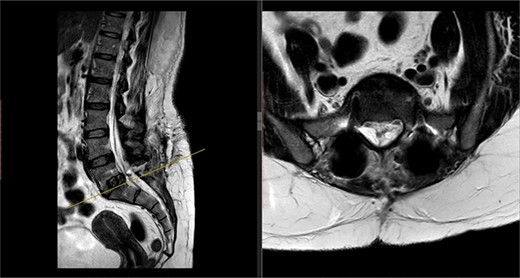

X-rays of the lumbar spine (Fig. 1) and pelvis performed in December 2015 showed a small idiopathic scoliosis in the lumbar spine. A magnetic resonance imaging (MRI) scan was performed in February 2016, which showed non-compressive disc degeneration and disc bulge at L4/5 and L5/S1. She was referred to physiotherapy for rehabilitation.

Preoperative X-ray of the lumbar spine performed in December 2015, confirming small idiopathic scoliosis in the lumbar spine.